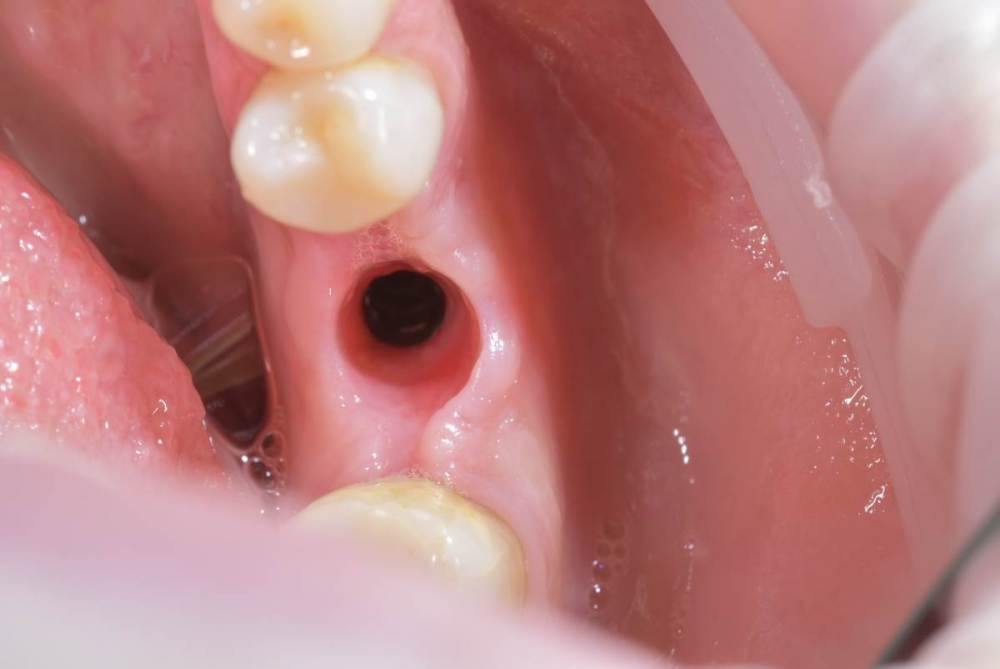

annda Опубликовано 1 октября, 2022 Поделиться Опубликовано 1 октября, 2022 На фото в аксиальной проекции показалось , что TL стоит:) А на снимке, совсем другой. Надо же, обман зрения. Ссылка на комментарий

TIGER Опубликовано 1 октября, 2022 Автор Поделиться Опубликовано 1 октября, 2022 (изменено) @annda да,вы про лунку?похоже,согласен,шейка широкая там 4.8 диаметр,но если присмотреться на внутренности видно,что это не SynOcta)А конус Изменено 1 октября, 2022 пользователем TIGER 1 Ссылка на комментарий